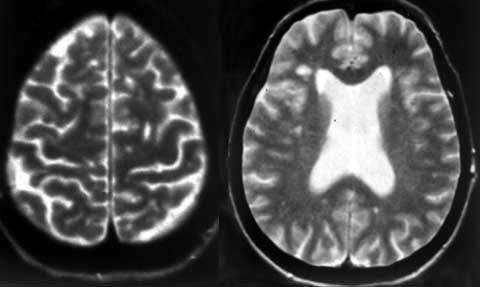

Оценка динамики активности ремиттирующего и прогрессирующего рассеянного склероза.

Рис. 1. Очаги демиелинизации в полушариях (слева) и стволе (справа) головного мозга с повышением и снижением интенсивности сигнала при ремиттирующий РС.